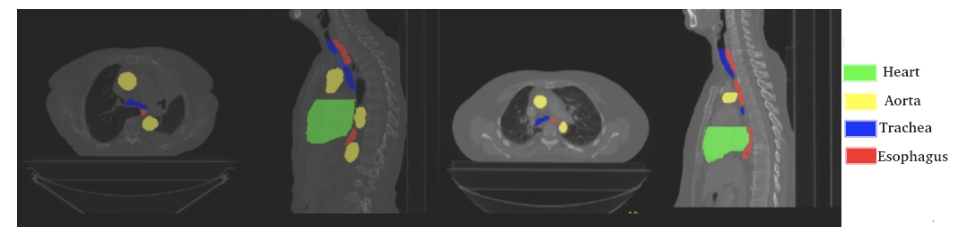

SegTHOR(危险胸腔器官分割)是一个专门用于胸腔危险器官 (OAR) 分割的数据集,即肿瘤周围的器官,在放射治疗期间必须避免受到辐射。 在此数据集中,OAR 是心脏、气管、主动脉和食道,它们具有不同的空间和外观特征。 该数据集包括 60 个 3D CT 扫描,分为 40 名患者的训练集和 20 名患者的测试集,其中 OAR 已由经验丰富的放射治疗师手动绘制轮廓。